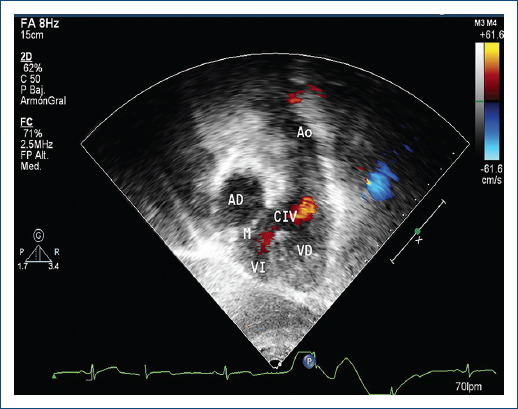

目的:心房-心室和心室-动脉双不协调(DD)或大动脉转位矫正术是一种罕见的心脏疾病,每1000个活产新生儿中就有0.02-0.07个患有此病。本研究旨在描述一系列 DD 患者的诊断、治疗和演变情况:方法:对过去 22 年中诊断出的 DD 患者的病历进行回顾性和描述性研究。研究采用了描述性统计方法。数字变量采用均值和标准差,分类变量采用频率和百分比:22 年中研究了 30 名患者,男性与女性的比例为 1.5:1,平均年龄为 20 个月。24/29(82.7%)名患者的病位为室间隔缺损。室间隔缺损是最常见的病变,占 25/29 例(86.2%),三尖瓣关闭不全占 70%。四名患者被诊断为肺动脉高压。20%的患者患有房室传导阻滞。一名患者患有沃尔夫-帕金森-怀特综合征。70%的患者接受了手术治疗。其中8人接受了格伦手术(26.6%),4人接受了丰坦手术(13.3%)。随访时间从1个月到17年不等。5人死亡(16.6%)。在随访的25名患者中,18名患者(72%)心室功能正常,5名患者为二级Ross分级(20%),2名患者为三级(8%):结论:这些患者的生活质量正在改善,但文献中对实施最合适手术的理想时间仍存在争议。

Results: Thirty patients were studied in 22 years with a ratio of 1.5:1 for men, with a mean age of 20 months. The situs was solitus in 24/29 patients (82.7%). Ventricular septal defect was the most frequent lesion in 25/29 (86.2%) Tricuspid insufficiency in 70%. Four patients diagnosed with pulmonary atrial hypertension. With atrio-ventricular block 20%. One with Wolff-Parkinson-White syndrome. Surgical treatment was carried out in 70% of patients. Eight with Glenn procedure (26.6%) and 4 with Fontan surgery (13.3%). Follow-up ranged from 1 month to 17 years. Five died (16.6%). Of the 25 patients in follow-up, 18 patients (72%) had normal ventricular function, 5 with Grade II Ross classification (20%) and 2 in Grade III (8%).